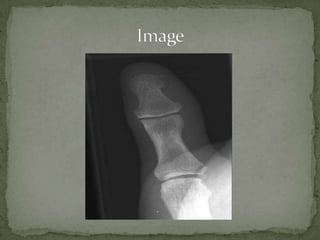

 Type 1 Skier’s Thumb

 Type 1Skier’s Thumb

Avulsion of UCL (ulnar collateral ligament) of the thumb

Also known as Skier’s thumb